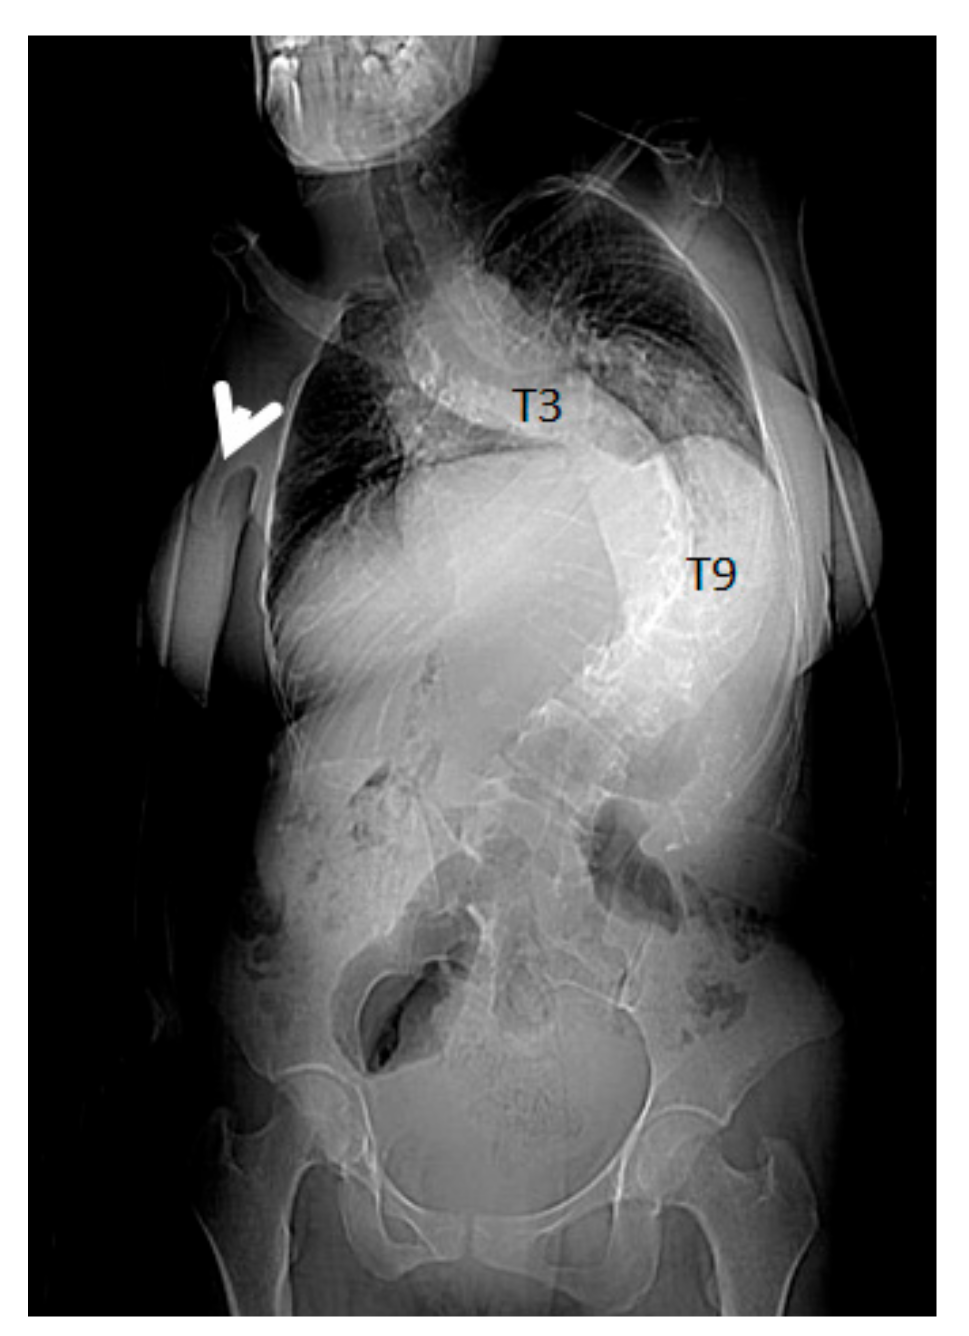

- A seven-year-old-boy was seen for the first time at the age of three years because of painful thoraco-lumbar kyphosis resulted from osteolysis of T9-L1. The left iliac crest was also involved in the pathological process of osteolysis (Figure 1). Back pain associated with Trendelenburg gait were the most bothersome symptomatology. Bone biopsy confirmed the diagnosis of Gorham-Stout disease. The kyphosis has been treated by a brace. Follow-ups showed stability of the kyphosis and dormancy of the osteolysis.